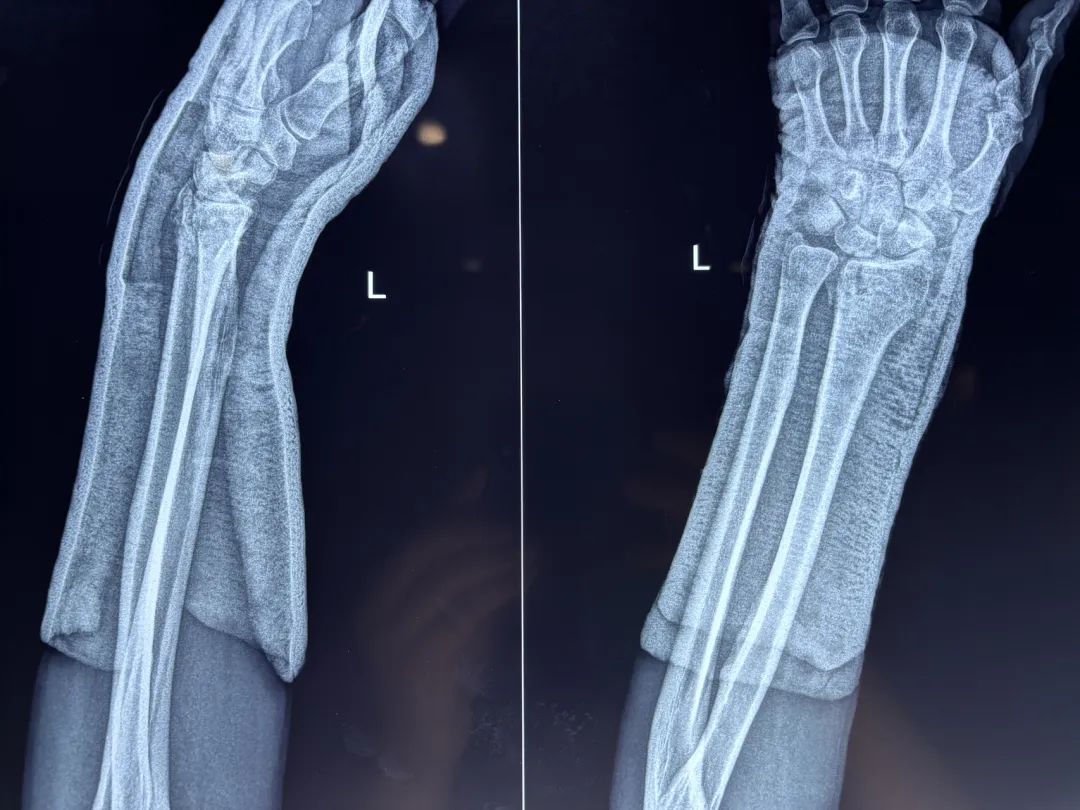

桡骨远端膨大,横断面略呈长方形,主要由松质骨组成,上端与桡骨干坚质骨相连,力学上是一个弱点,故此处易骨折。

桡骨茎突较尺骨茎突长约1~1.5cm,故桡骨远端关节面向尺侧倾斜15°~30°(平均 23°),还向掌倾斜 0°~23°(平均 11°)

桡骨远端关节面的倾斜角度 :

正常桡骨远端关节面向掌侧倾斜0°~23°平均11°

正常桡骨远端关节面向尺侧倾斜15°~30°,平均23°( 桡骨远端骨折后,其关节面的倾斜度改变)